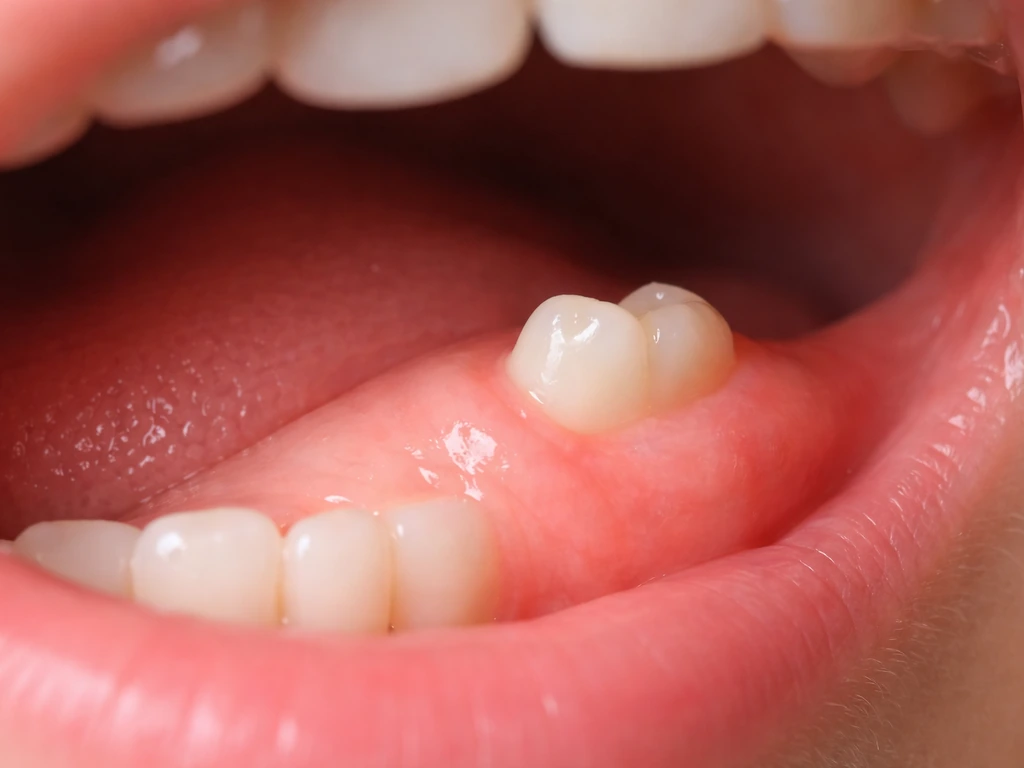

Delayed eruption happens when a tooth has formed normally but is taking longer than expected to push through the gum. Common causes include crowding (not enough space), a retained baby tooth sitting in the way, a thick gum layer over the tooth, or a benign cyst. Impaction is more serious: the tooth is physically blocked and cannot erupt on its own. Wisdom teeth are the most common example, but canines are actually the second most commonly impacted teeth in the mouth. If you are wondering about how to make wisdom teeth grow in faster, the honest answer is that you mostly cannot, but a dentist can tell you whether the tooth is on track, impacted, or needs to be addressed.

Operculectomy for wisdom teeth

If a wisdom tooth is partially erupted but a thick flap of gum (operculum) is covering it, a minor surgical procedure can remove that flap and allow the tooth to erupt more cleanly. This is only appropriate when the tooth is actually in a good position and has room to come through, which is not always the case with wisdom teeth.